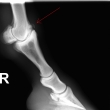

Čip ve spěnkovém kloubu na pánevní končetině

Ankylóza spěnkovýho kloubu

rentgenologické vyšetření